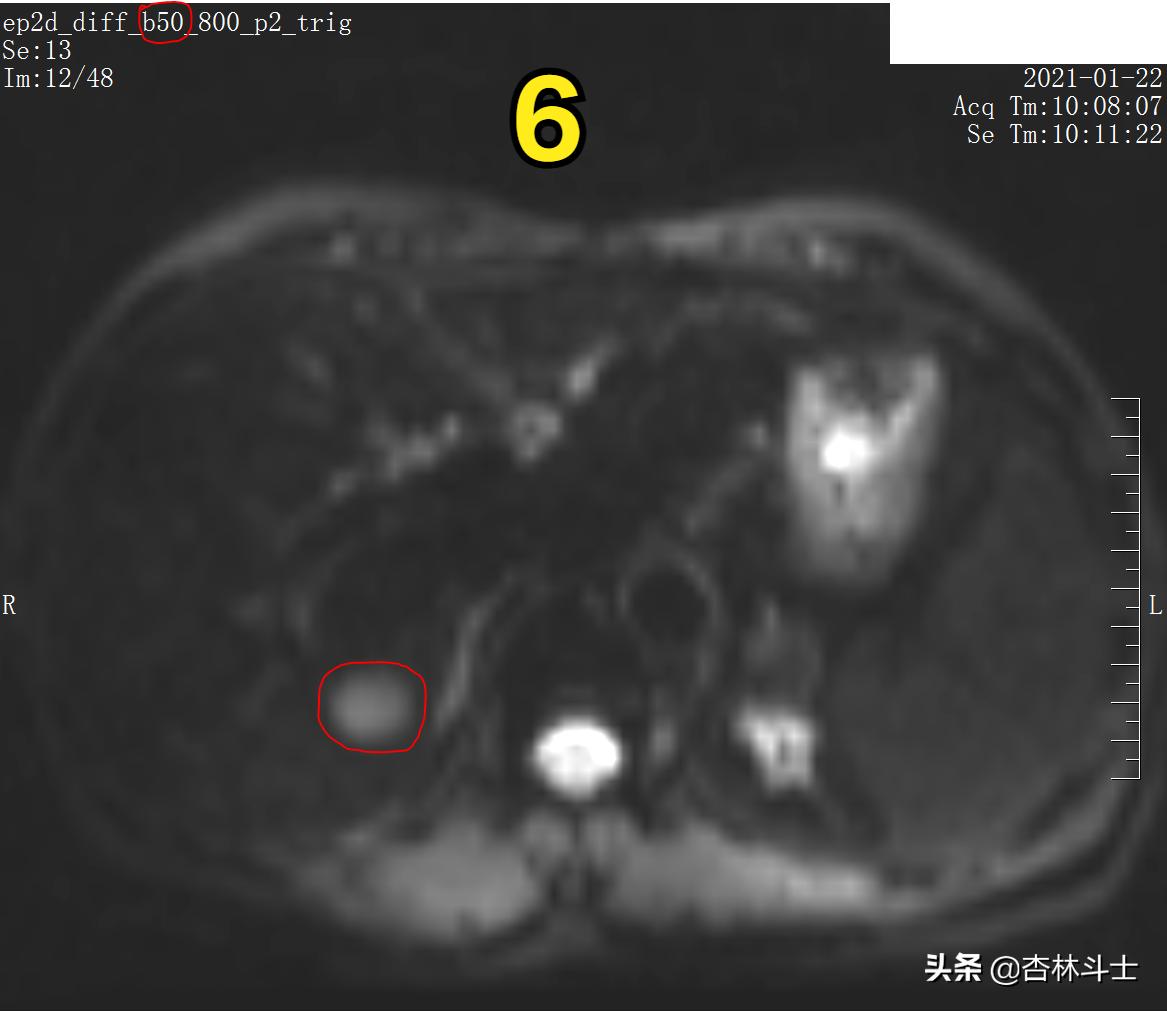

图6 DWI b50

图6 为低b值弥散加权图像(DWI)

图7 DWI b800

图7 为高b值弥散加权图像(DWI),病灶呈高信号。此序列目的为了解人体内水分子“布朗运动”情况,肿瘤病灶内细胞密度高,肿瘤细胞代谢旺盛,细胞内细胞器多,细胞核大,种种原因,限制了肿瘤组织内的水分子运动,使得肿瘤病灶在DWI上呈高信号。

b值越高,越凸显身体内水分子弥散受限程度。

图6、7为弥散加权像,新发病灶在弥散加权上弥散受限,呈高信号。